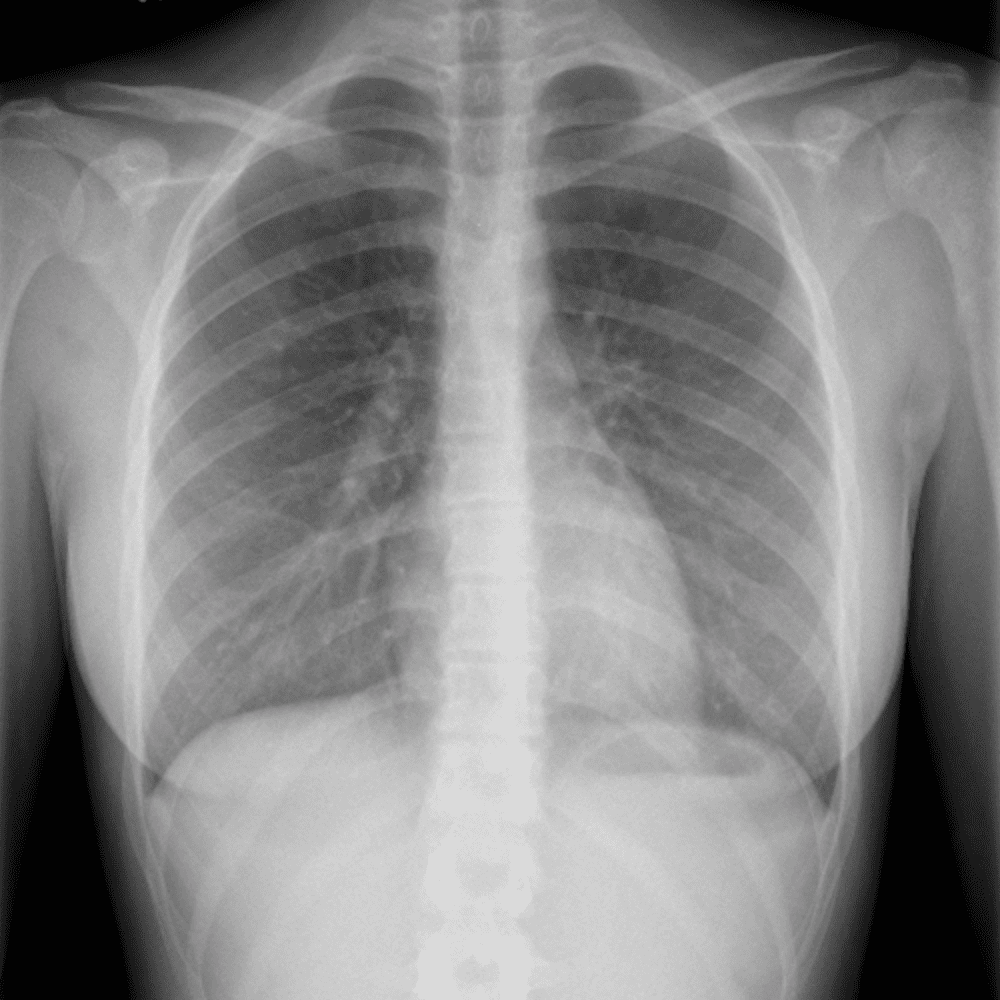

Peds Chest

Practice

Simulates call by including subtle or difficult cases and some normals.

50 cases